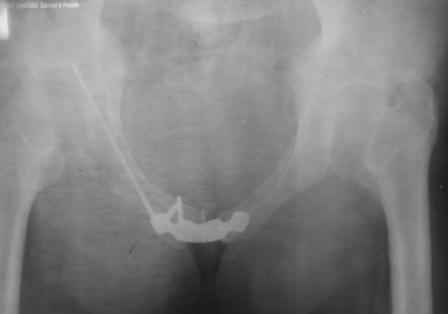

Ерсин 11 Апрель 2010, 21:14

Уважаемые коллеги! спасбио Вам за советы и наставления! Рукводство получил, шикарно, отдельно спасбио А.Н.! Пациента сегодня активизировали, спокойно ходить с полной опорной нагрузкой. С уважением Ерсин Жунусов.

доступ.jpg

73KB (75258 bytes)

X-ray!

x-ray.jpg

33KB (34105 bytes)